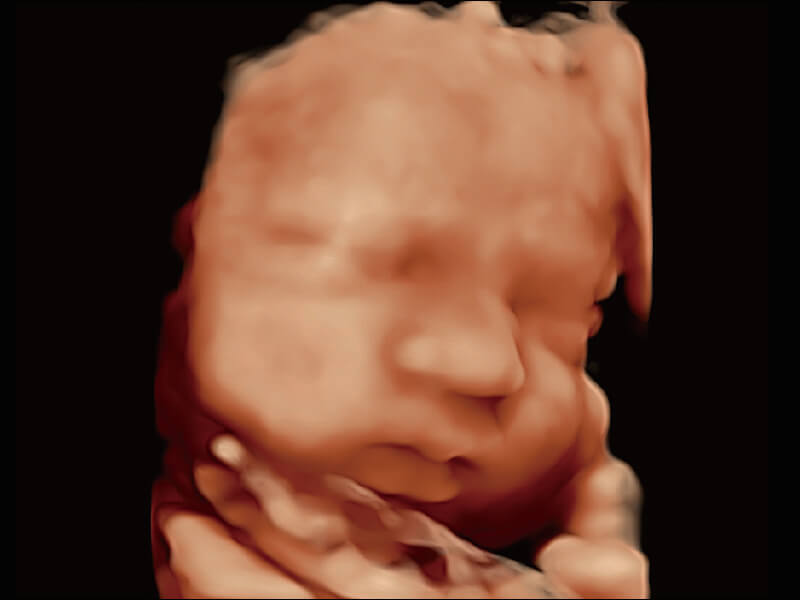

高分辨率容积成像 栩栩如生

超宽频带技术,为容积成像带来优质的二维图像基础,为您呈现丰富的结构细节,栩栩如生地展示宝宝的宫内形态以及各种组织的立体结构。